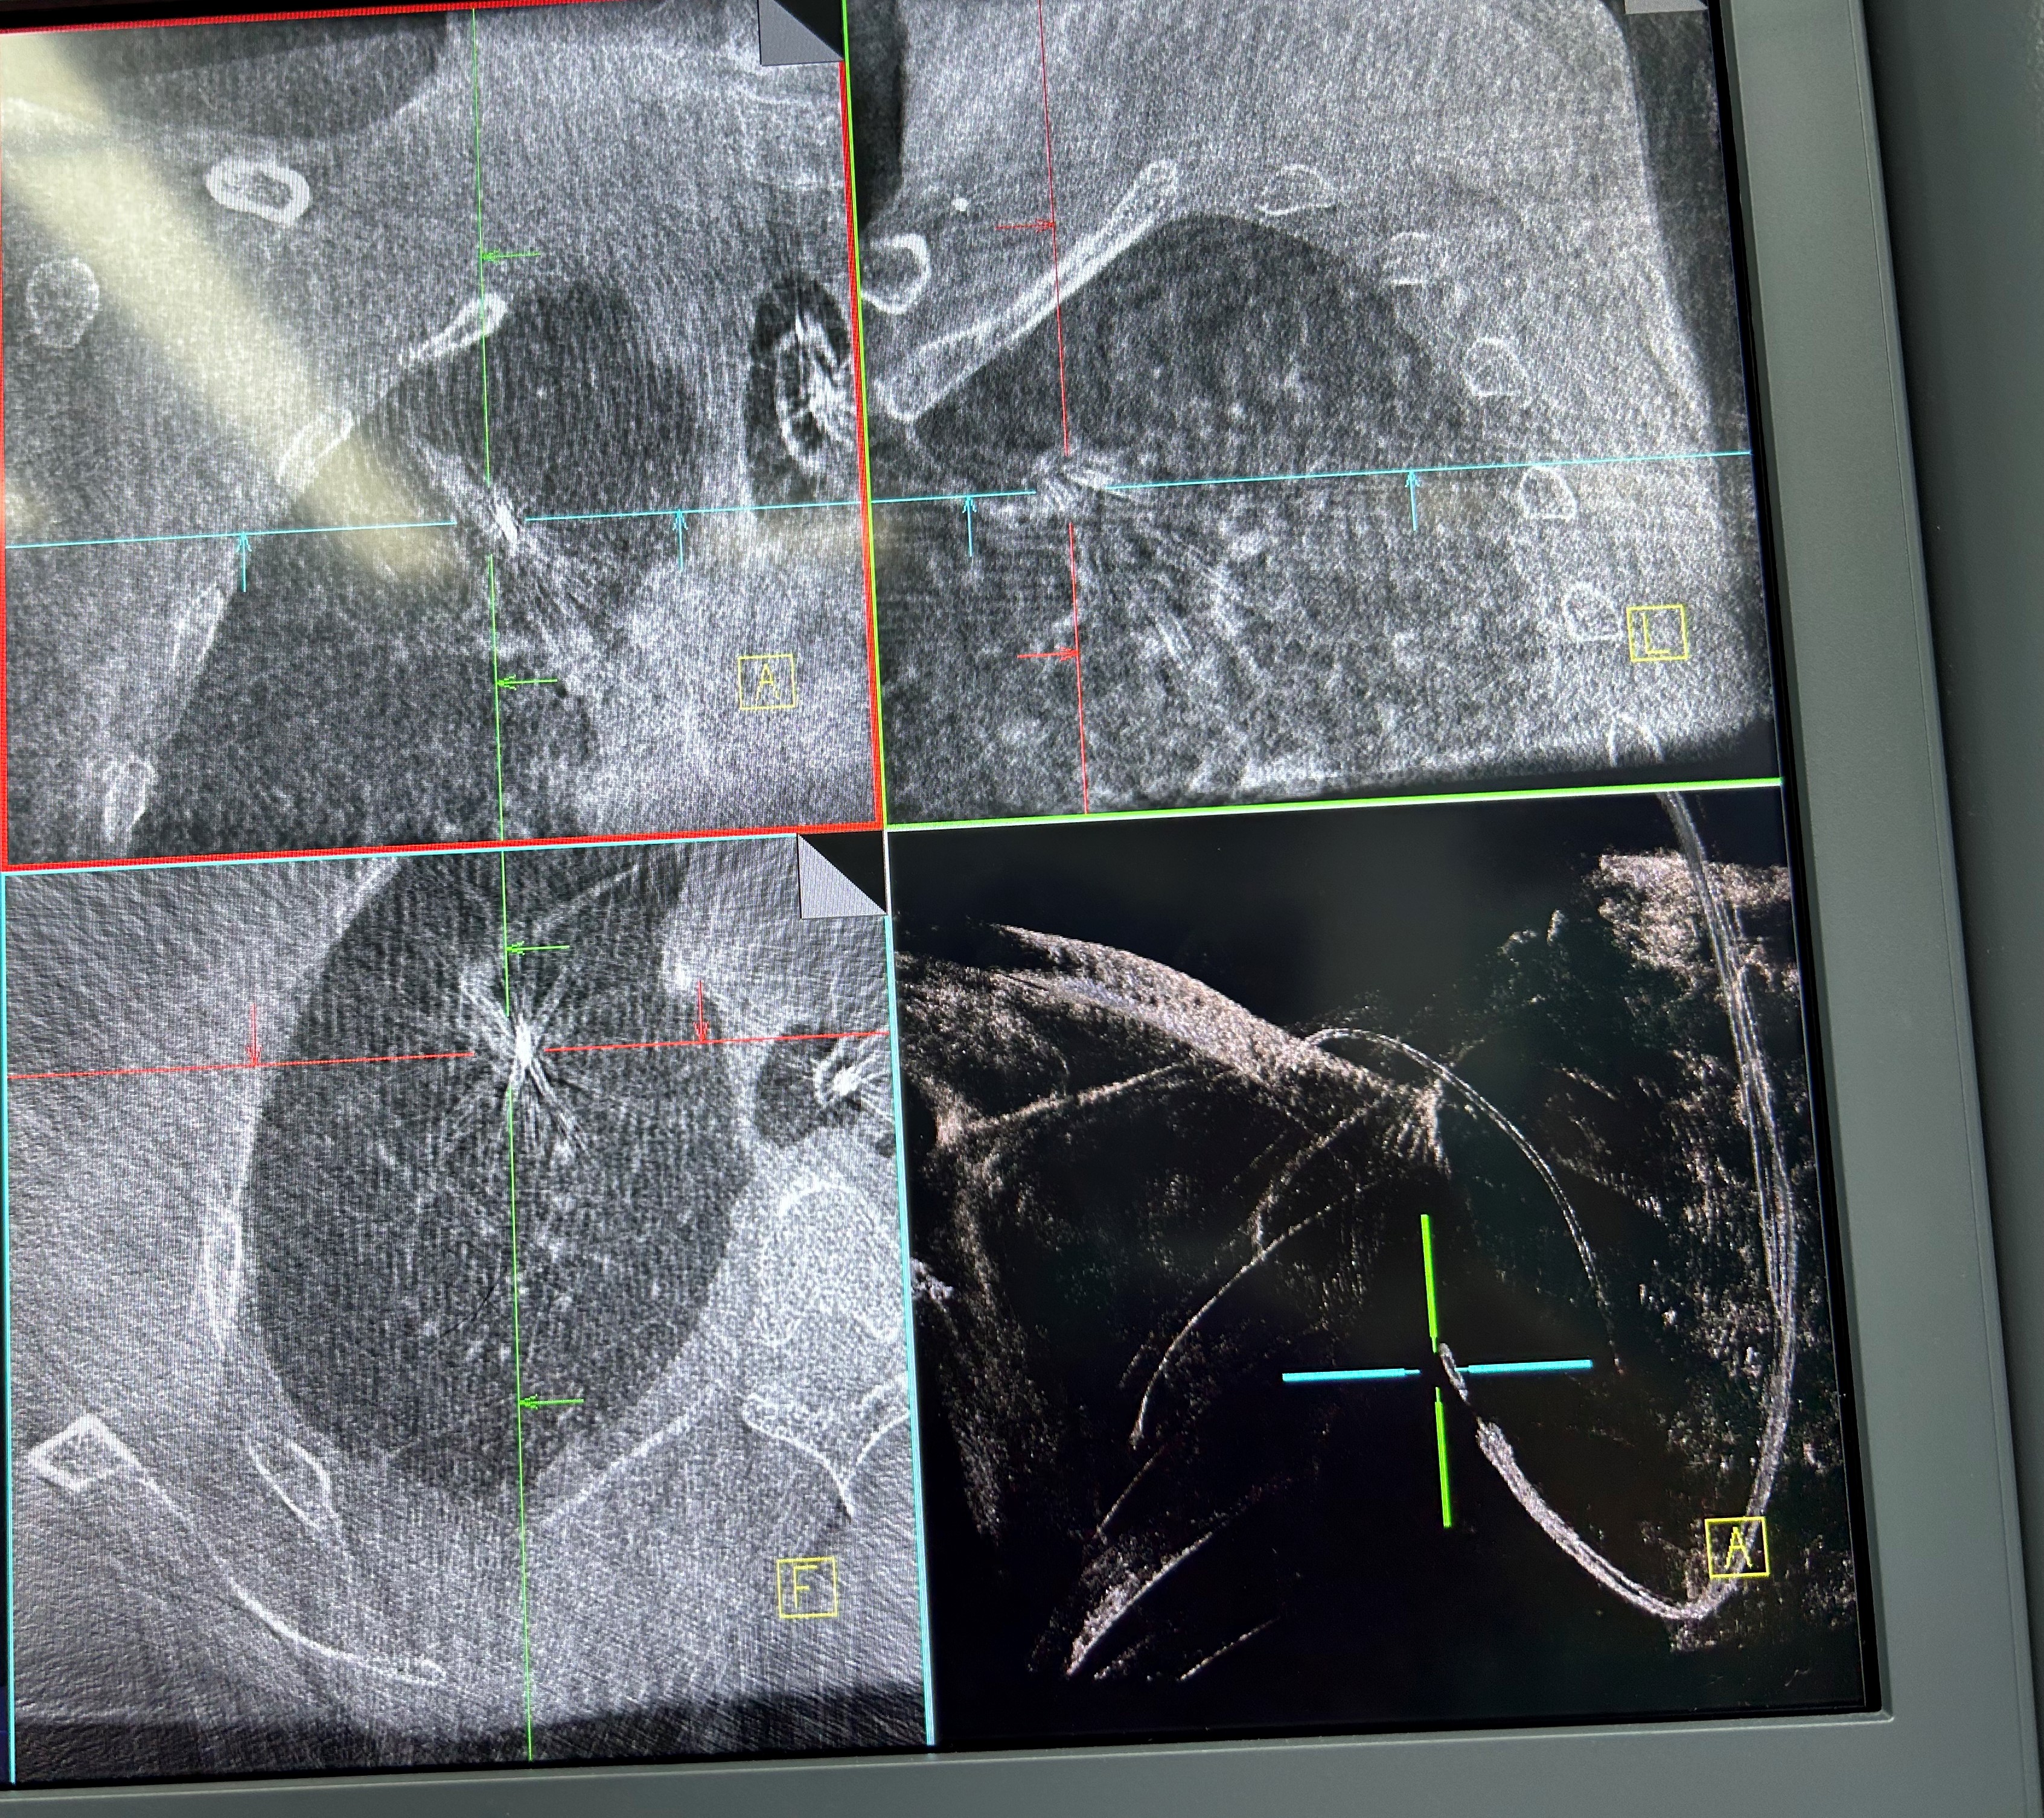

手术当日,呼吸科团队帮助患者在全麻下完成气管插管,手术由蒋军红主任指导,负责手术方案的实时优化与安全保障。曾大雄主任医师和王兰主任医师精准操作机器人支气管镜,在支气管镜导航机器人的精准引导下,通过AI三维重建、智能路径规划以及多模态信息融合,将支气管镜精准“引导”至右上叶尖段病灶处。随后,团队启动CBCT(锥形束计算机断层扫描)通过实时影像复核确认靶病灶,实现病灶“毫米级”精准锁定,彻底解决肺部病灶“找不到、找不准”的核心难题。机器人气管镜导航技术实现了从术前规划到术中操作全流程的智能精准控制,真正做到了肺部病灶的精准覆盖。

明确肿瘤诊断后,治疗方案即刻启动。团队经导航引导鞘管,精准插入一次性冷冻消融针(直径仅1.9mm)。再次通过CBCT确认消融针完全“扎根”于右上叶尖段病灶内后,开启冷冻治疗模式:以-160℃深低温冷冻10分钟、复温至45℃维持3分钟为一个治疗循环。完成了3次循环后,为确保病灶无遗漏,团队微调消融针位置,再次追加2次循环治疗。术后复查CBCT显示,病灶已呈现典型的冷冻后改变,术后两天复查胸部CT提示消融范围满意,治疗效果完全达到预期。整个手术过程中,患者生命体征始终平稳,术后第二天即可下床活动,真正实现了“微创治疗、快速恢复”的目标。

治疗前